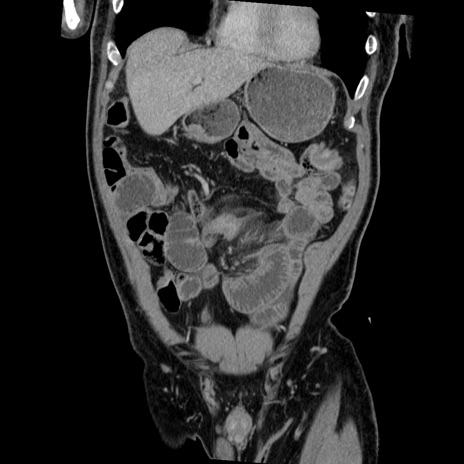

症例22(冠状断像)

【症例】50歳代男性

【主訴】腹痛

【現病歴】AVMからの被殻出血のため回復期リハ病棟入院中。 本日午後3時頃急に下腹部痛が出現した。

【既往歴】AVM、被殻出血、虫垂炎、高血圧

【身体所見】意識晴明、左半身不全麻痺、会話の理解は良好、36.5°C、腹部:膨隆、全体に板状硬、下腹部正中に圧痛点あり、反跳痛-、筋性防御不明、右下腹部にope scar

【データ】WBC 9400、CRP 0.06

横断像